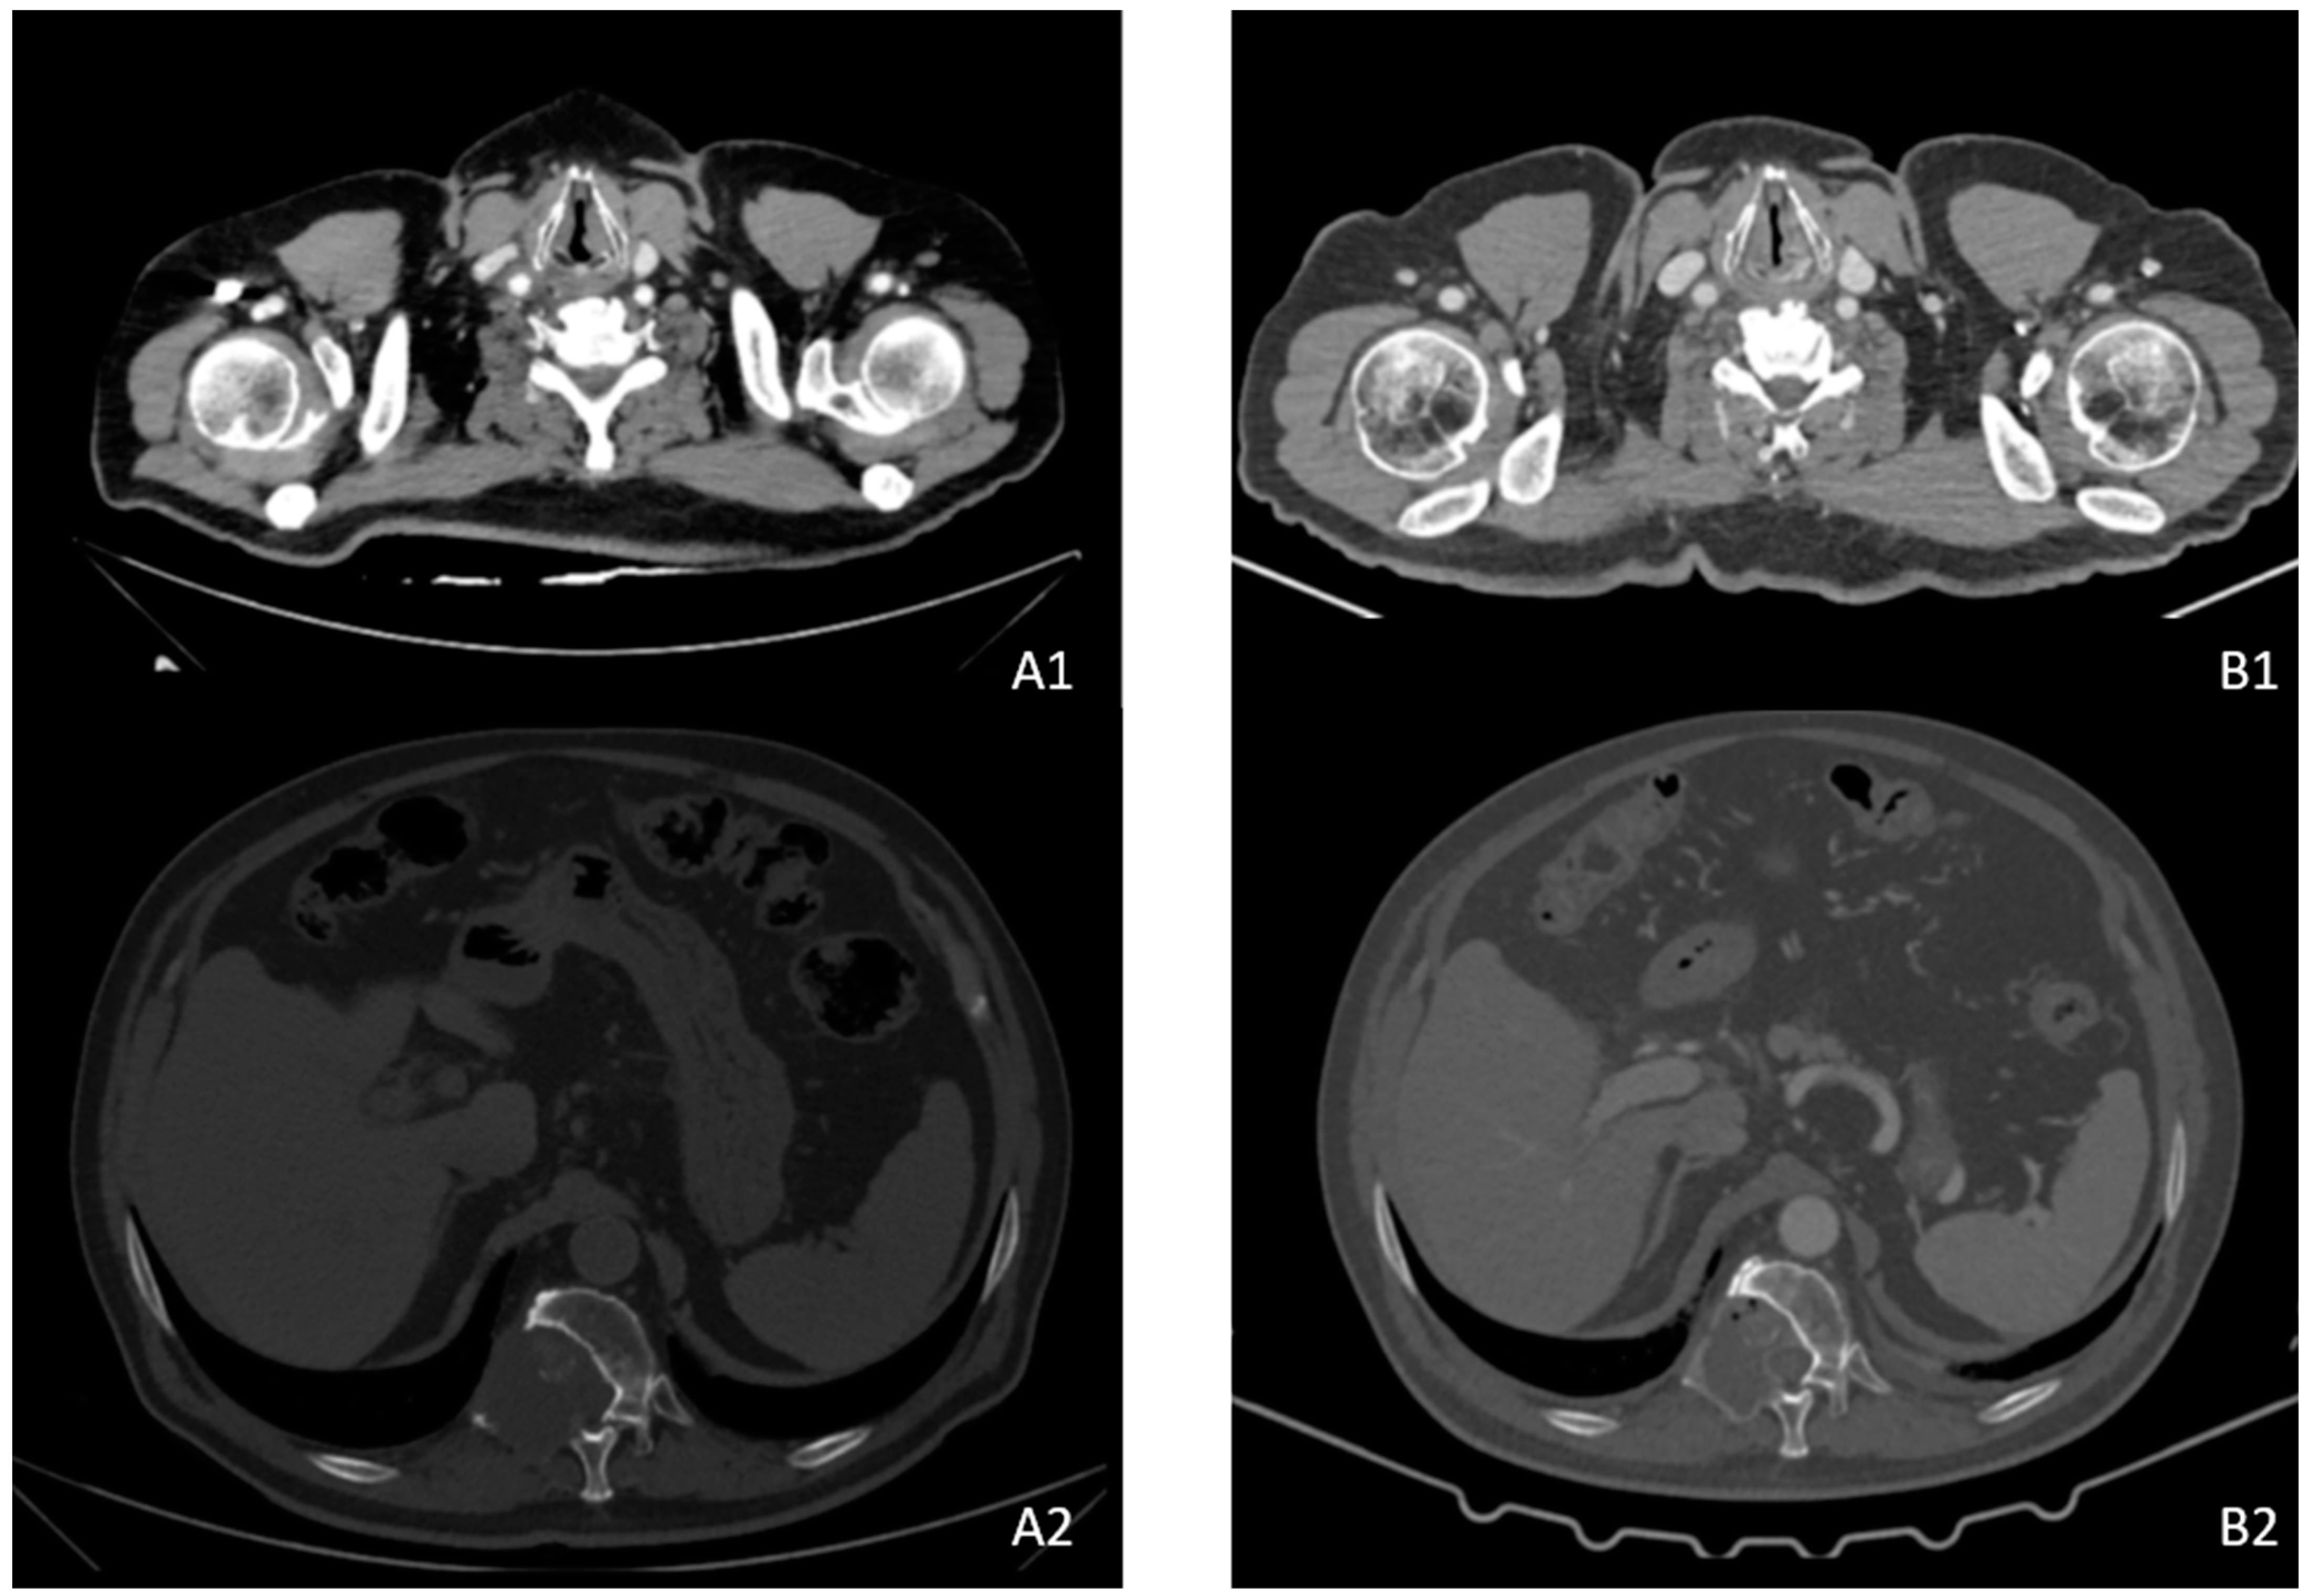

2. Case Description